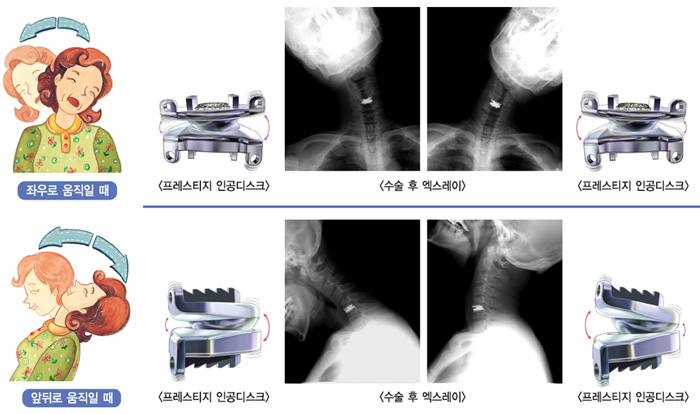

● 인공디스크 교체술 ● 소개 디스크 탈출증 있는 환자 분에서 비수술적 치료로 조절되지 않는 통증이 있을 때 시행합니다. 경부 앞쪽으로 접근하여 가로 3~4cm 정도 절개하게 되며 터진 디스크를 제거 하고 인공 디스크를 삽입하여 원래 디스크의 70~80% 기능을 보존할 수 있습니다. ● 장점 - 수술 후 회복이 빠르며(약 2주) 직장 복귀가 빠른 수술 방법입니다. - 짧은 수술 시간(약 1시간)과 짧은 보조기 착용 기간(약 2주) ● 적응증 - 디스크 탈출증 - 경한 척추 협착증 - 요추 인공 디스크 교체술은 매우 적응증이 좁습니다. (전문가와 상의) ● 목 디스크 질환 나이가 들면서 디스크 내의 수분이 빠져나가 그 높이가 줄어들고, 척추 뼈 옆의 신경이 지나가는 통로가 좁아져서 신경을 압박하여 나타나는 질환을 퇴행성 질환이라고 합니다. 퇴행성 변화가 지속되면 수핵이 딱딱해지고, 섬유륜이 쉽게 찢어져 수핵이 척추관 내로 탈출하여 척수나 신경을 압박하는 추간판 탈출증이 오기 쉽습니다. ▶ 대체적으로 많은 환자들이 다음과 같은 증상을 호소합니다. - 목이나 목 주위의 근육이 뻣뻣하다. - 손가락이 저리고 아프며 등 뒤나 견갑골 사이에도 통증을 느낀다. - 목은 아프지 않지만 어깨와 팔을 따라 저리기도 하고, 힘이 없다. - 심한 경우에는 팔다리의 마비나 사지운동 약화로 보행장애를 보이기도 한다.